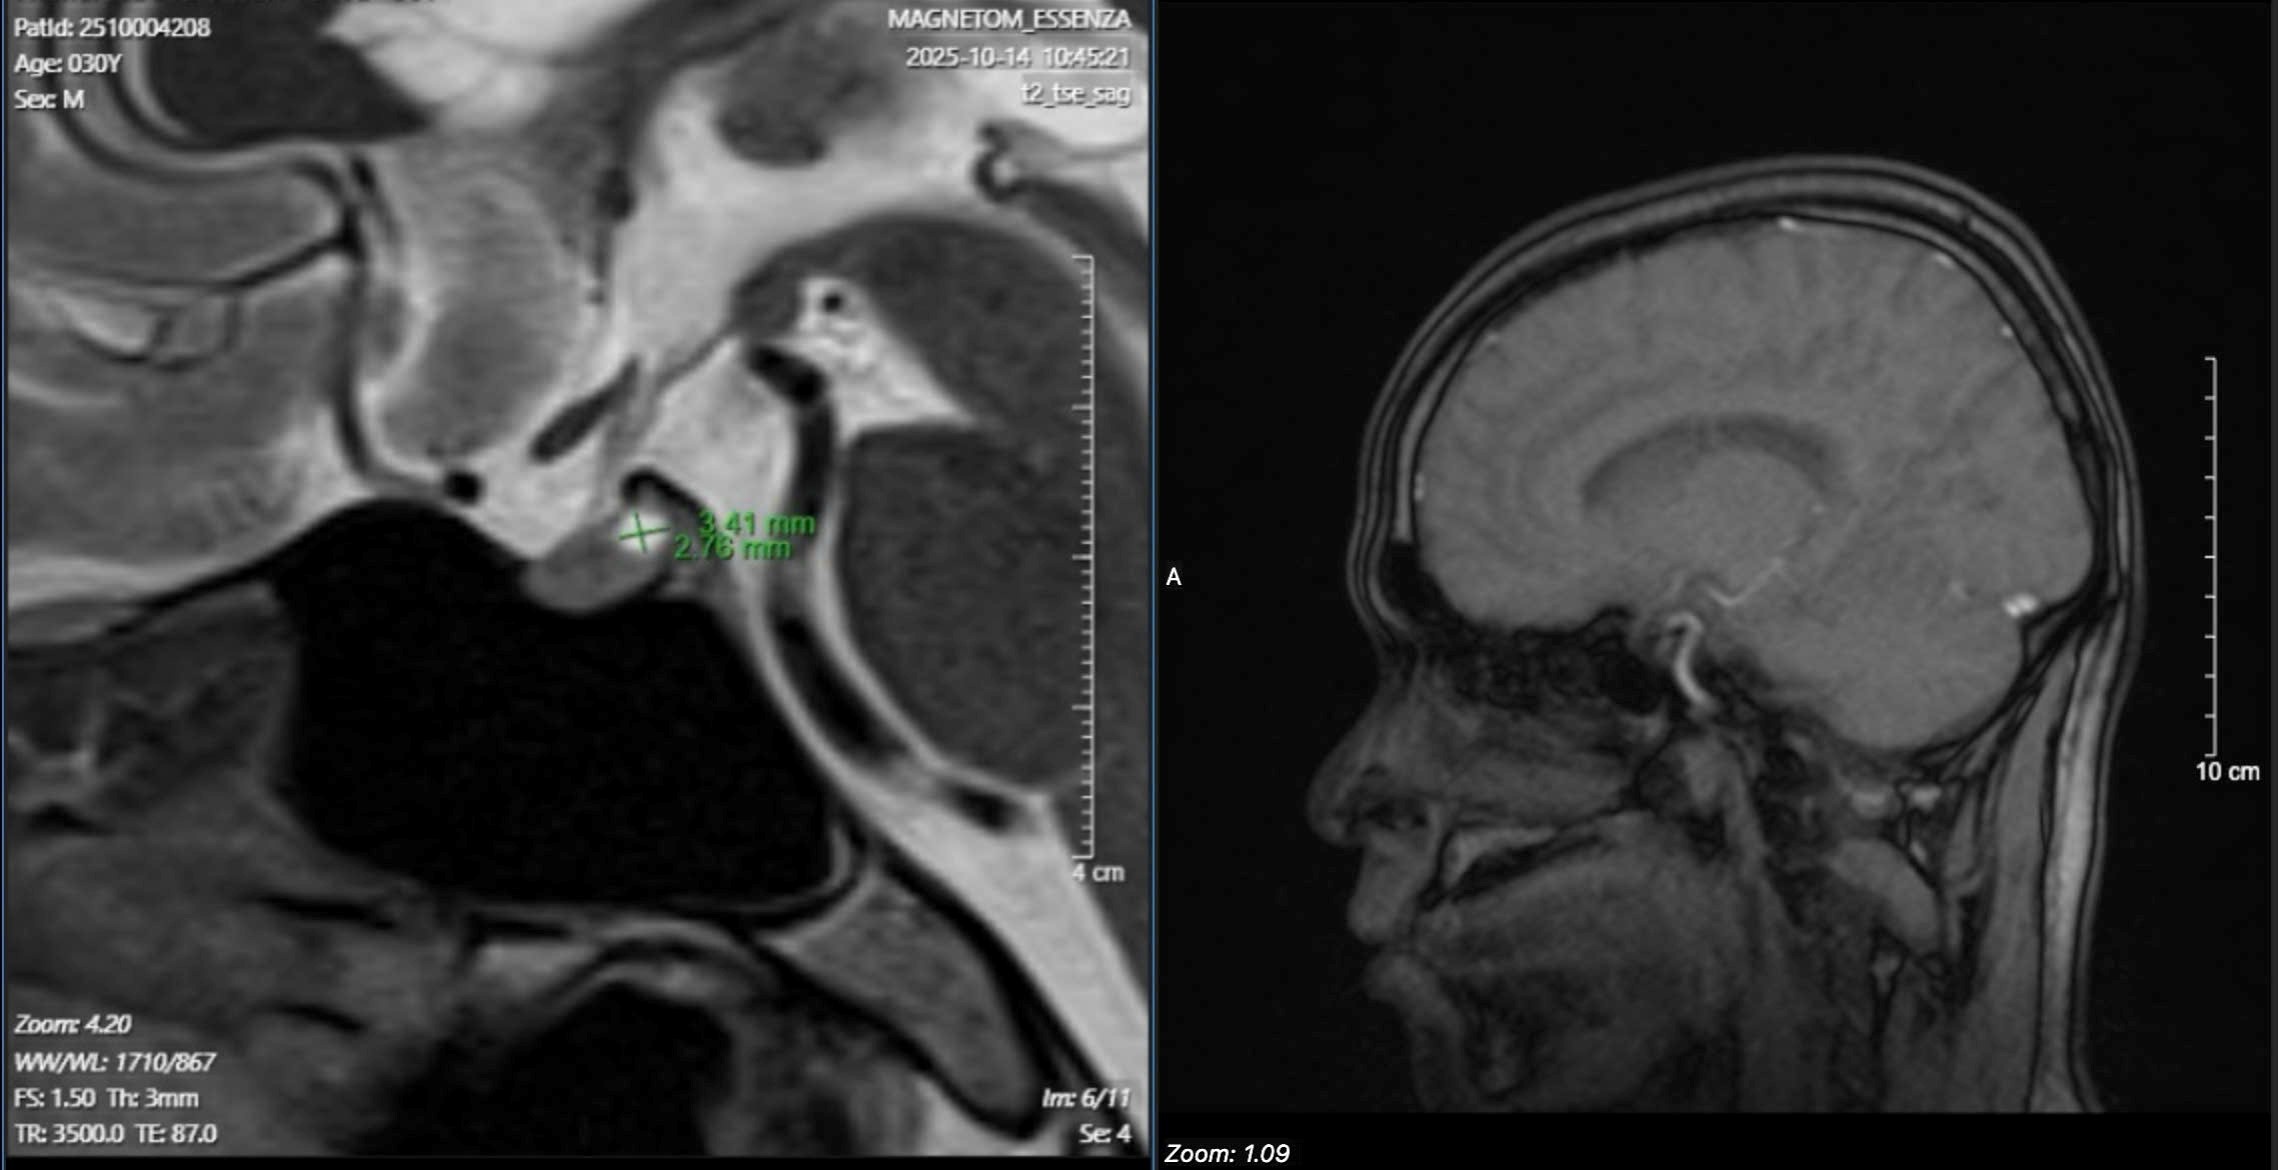

Để tìm nguyên nhân, các bác sĩ chỉ định chụp MRI sọ não, kết quả phát hiện anh T. có u tuyến yên - một khối u lành tính nằm ở đáy não, có thể ảnh hưởng đến toàn bộ hệ thống nội tiết.

Hình ảnh khối y tuyến yên của bệnh nhân N.V.T.. Ảnh: BSCC.